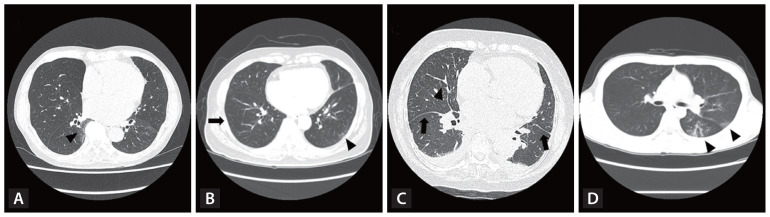

Interstitial lung abnormalities (ILAs) are early indicators of interstitial lung disease, often identified incidentally via computed tomography of the chest. This review explores the diagnostic criteria for ILAs as outlined by the Fleischner Society, highlights associated risk factors, examines their impact on patient outcomes, and discusses management strategies. The prevalence of ILAs varies significantly, ranging from 3% to 17% across populations. Key risk factors include advanced age, smoking status, and underlying genetic predispositions. Recent advancements in imaging analysis, particularly through automated quantitative systems, have enhanced the accuracy of ILA detection. Although often subtle in presentation, ILAs hold clinical significance due to their associations with impaired lung function, progressive fibrosis, and increased mortality. Therefore, monitoring and management plans should be individualized to the risk profile of patients. Further studies are needed to refine ILA diagnostic criteria, enhance our understanding of their clinical implications, and establish optimal timing for therapeutic interventions.